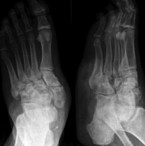

Wichtig und unerlässlich ist daher immer zunächst ein Röntgenbild des Fußes in drei Ebenen, wobei ap. und seitl. eine Belastungsaufnahme als Standard gilt. Hier kann man die Fehlstellungen, die es zu adressieren gilt, sehr gut erkennen und dann operativ adressieren. Weiterführend sind bei Rückfußdeformitäten eine Saltzman-Aufnahme bis hin zur Ganzbeinaufnahme zielführend, um das "Centre of rotation and axis" (CORA) zu bestimmen.

Gelingt dies nicht, so sollte man wie Hochlehnert und Engels es im Buch das Diabetische Fuß-Syndrom beschreiben "keine Angst vor der kleinen Chirurgie beim neuropathischen Fuß" haben. Gerade Deformitäten wie Hallux valgus, Hammer- und Krallenzehen sowie die Plantarisierung (wenn Abschnitte der Zehen zur plantaren Auflagefläche werden) können mittels minimalinvasive Chirurgie sehr gut auch beim Diabetischen Fuß-Syndrom behandelt werden.

Die Plantarisierung entsteht durch Hyperflexion der Zeheninterphalangealgelenke D2-5 oder auch durch Hyperextension des IP-Gelenkes bei Hallux rigidus. Hochlehnert und Engels berichten, dass ca. 40 % der Patienten in ihrer Fußambulanz solche Langzehenfehlstellungen haben. Biomechanisch kommt dies durch Ausfall der intrinsischen Fußmuskulatur im Rahmen der Polyneuropathie.

57,8% aller Ulcera treten laut Engels im Bereich der Zehen auf. Chirugisch lässt sich dies ambulant mittels Tenotomien der langen Flexorensehne bei Krallenzehe, bei flexiblen Hammerzehen per Tenotomie des Extensor brevis lösen. Besteht eine rigide Hammerzehenfehlstellung, so wird hier eine sequentielle Hammezehenkorrektur operativ durchgeführt. Zunächst erfolgt die Condylektomie des Basisgliedes am Mittelgelenk, bis zum Kapselrelease im Grundgelenk.